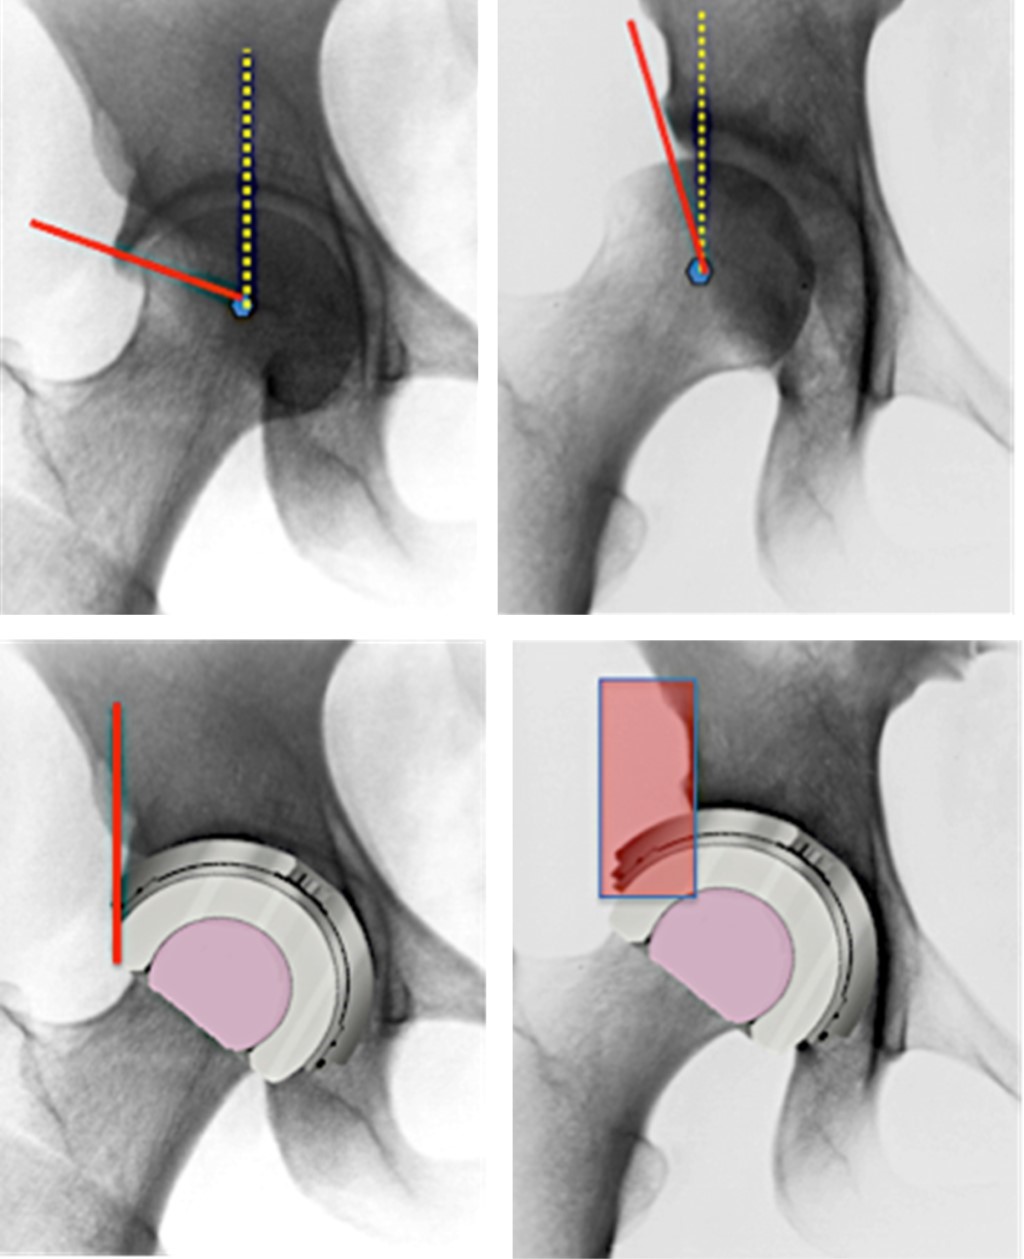

Por otra parte, el empleo de estos diseños no es inocuo. Sabemos que la inclusión de "cejas" en los insertos o las copas acetabulares "estándar" traen como consecuencia efectos en los arcos de movilidad y en los riesgos de colisión entre sus componentes, sea cual sea el tipo de inserto utilizado (Figura 1), por lo que de no entender con claridad el papel que desempeñan para prevenir luxación, pudiendo ser una ayuda, puede convertirse en una calamidad por sus efectos en los arcos de movilidad y por el riesgo de colisión entre el borde del inserto versus el cuello del vástago. Estos problemas pueden ser provocados principalmente por errores en el posicionamiento y orientación de la copa o del inserto, en especial cuando se emplean en vástagos con diseños de cuello voluminosos o por la falta de una adecuada relación cabeza-cuello.15 También debe comentarse que hasta ahora no hay un consenso en cuanto a cuál es la posición óptima para orientar el "labio", por lo que los insertos se colocan según el criterio clínico-quirúrgico del cirujano para cada caso en particular.

Con relación a la capacidad de diversos modelos contemporáneos para prevenir la luxación y mejorar los arcos de movilidad. Nevelos y colaboradores19 hicieron un estudio comparativo in vitro utilizando simulación computarizada estática y tridimensional para investigar los efectos que tienen diversos diseños en la distancia de dislocación horizontal posterior (DDHP) y los arcos de movilidad. Compararon las copas estándar versus copas de DM semiesféricas, modulares y anatómicas.

Estos autores observaron que las variaciones en el diseño tuvieron mayor efecto en la distancia de luxación horizontal posterior (DLHP) que en el incremento en el tamaño de la cabeza en cada diseño específico (p < 0.001) (Tabla 1 y Figura 7). También observaron que los diseños de DM anatómicos así como las versiones modulares tienen mayores distancias de DLHP que los diseños de DM subhemiesférica y que los insertos fijos hemiesféricos estándar (p < 0.001). Otro de sus hallazgos es que el incremento en el tamaño de la cabeza aumenta las DLHP en todos los diseños (p < 0.001). Asimismo, encontraron que el implante subhemiesférico es el que tiene el mayor rango de movilidad libre de pinzamiento (p < 0.001; R2 = 0.86) entre todos los diseños estudiados.

Observe que en la Tabla 1 y en la Figura 7 que el tamaño del cótilo y el tamaño de la cabeza no afectan significativamente a la DLHP, pero el aumento en el diámetro de la cabeza sí la aumenta; lo mismo sucede con el incremento en el techo de la cúpula, ya que se aumenta DLHP (capacidad de retención). Es importante observar que la DLHP y el rango de movilidad libres de pinzamiento no pueden aumentarse a la vez. Por lo anterior debemos estar atentos al tipo de copa de doble movilidad que utilizaremos, ya que todos tienen distintos atributos en relación con los riesgos de luxación y de rangos de movilidad.